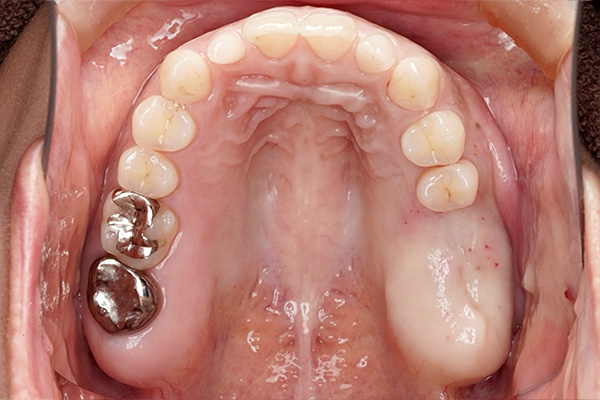

【札幌駅前】40代・女性奥歯が咬めない骨が少ない

上顎骨3mm→13mmへ増やしたサイナスリフト(骨造成)症例

| 主訴 | 左上に歯を入れたい |